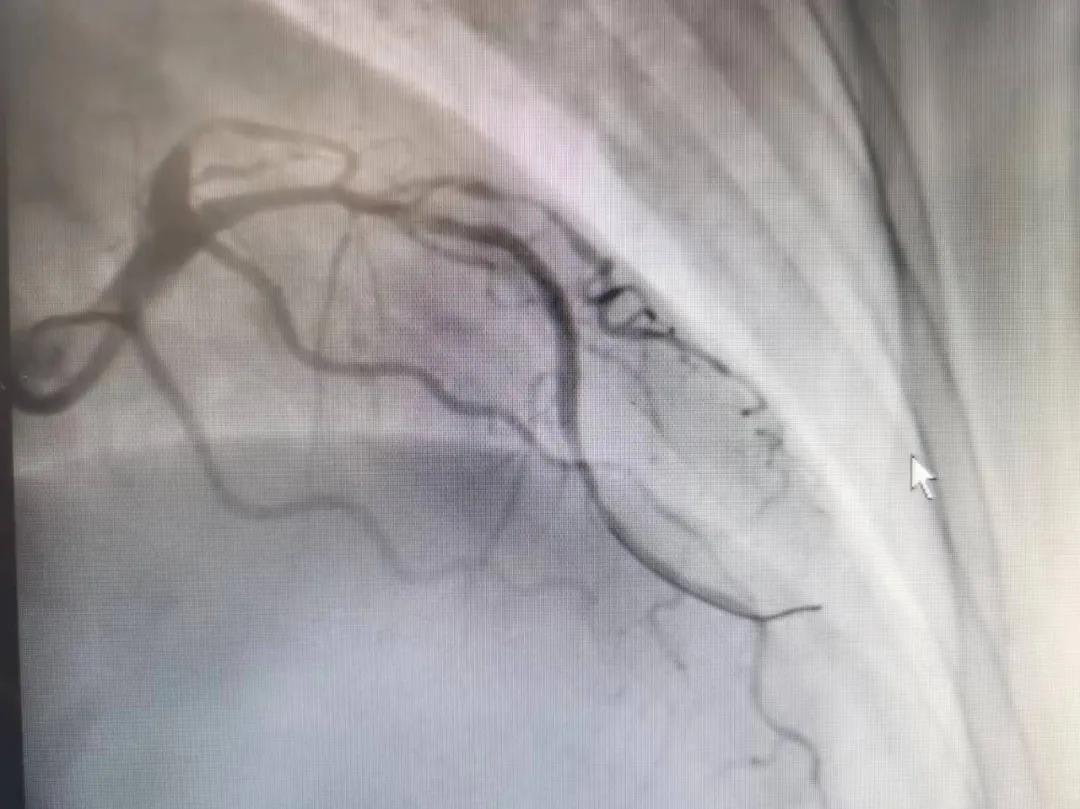

王瑾院長和李慧新主任帶領介入團隊充分評估,決定行前降支冠狀動脈鈣化病變旋磨術,術中應用1.5mm旋磨頭,以15萬-17萬轉/分速度共對病變旋磨3次,累計旋磨時間60秒,后復查造影示鈣化明顯減輕,為后續(xù)操作創(chuàng)造了良好條件,隨后應用預擴張球囊、切割球囊再次處理病變,并順利植入支架1枚,復查造影顯示支架膨脹及貼壁良好,無夾層、血腫、慢血流等情況,手術順利完成?;颊咝g后無不適,胸悶、胸痛癥狀明顯緩解,順利出院。

術后